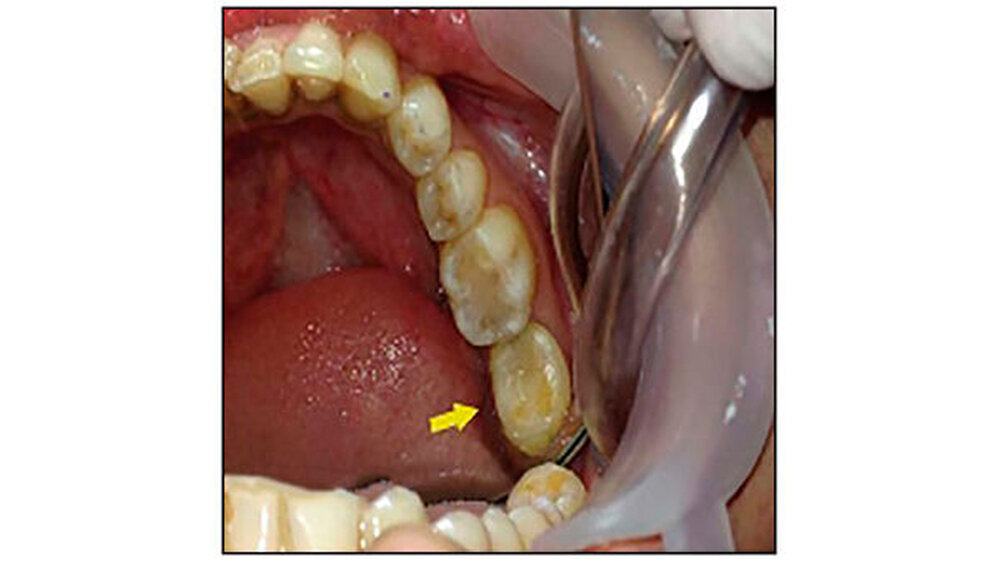

Eine 27-jährige Patientin stellte sich mit Schmerzen im linken Unterkiefer in der Abteilung für Zahnerhaltung und Endodontie am Himachal Dental College in Himachal Pradesh , Indien, vor. Die klinische und radiologische Untersuchung ergab, dass der Zahn 37 stark kariös war. Zudem lag eine chronische irreversible Pulpitis und apikale Parodontitis vor. Der Zahn 38 zeigte horizontale Einbrüche (Abbildung 1). Daher wurde beschlossen, 37 und 38 gleichzeitig zu extrahieren und den 38 in die Extraktionsstelle des 37 zu transplantieren.

Die Anästhesie erfolgte mit Lidocain-Hydrochlorid (Lignox zwei Prozent, Indoco-Remedies Ltd., India). Zuerst erfolgte die Extraktion von Zahn 37 extrahiert - ohne die Corticales zu beschädigen. Danach erst erfolgte die Extraktion von Zahn 38, um hier die Gewebeschäden so gering wie möglich zu halten. Eine horizontale intrakrevikuläre Inzision wurde durchgeführt. Zahn 38 wurde bis zur Transplantation in isotoner Kochsalzlösung gelagert, parallel eine Socket Preparation vorbereitet (Abbildung 2).